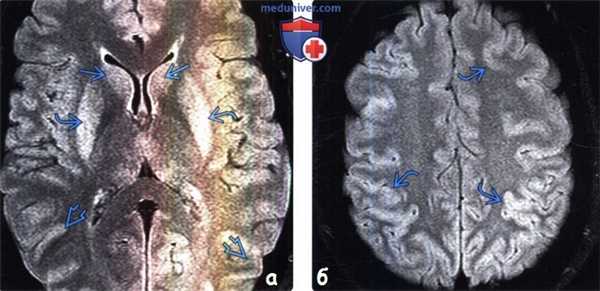

(а) МРТ, FLAIR, аксиальный срез: у женщины 22 лет, найденной без сознания после вдыхания дыма при пожаре в жилом помещении, определяется повышение интенсивности сигнала от скорлупы билатерально, хвостатых ядер и коры больших полушарий .

(б) MPT, FLAIR, аксиальный срез: у этой же пациентки определяется распространенное набухание коры и легкое повышение интенсивности сигнала от нее.

(а) МРТ, ДВИ, аксиальный срез: в скорлупе билатерально, хвостатых ядрах и коре больших полушарий визуализируются соответствующие вышеописанным изменениям на FLAIR зоны ограничения диффузии.

(б) МРТ, ДВИ, аксиальный срез: у того же пациента определяются протяженные участки ограничения диффузии в области коры больших полушарий. Наблюдаемые изменения более выражены на ДВИ по сравнению с FLAIR. Несмотря на то, что данные рентгенологические признаки неспецифичны, их двусторонний и симметричный характер должен вызывать подозрение на системное гипоксическое/токсическое/метаболическое поражение. Для подтверждения диагноза чрезвычайно важное значение имеет анамнез заболевания.